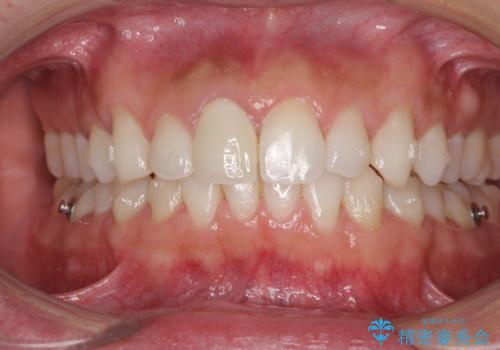

口が閉じにくい インビザラインによる矯正治療

- 口の閉じにくさを気にして来院された患者様です。

患者様と相談の上、横顔の印象から抜歯矯正は必要ないと判断し、IPR(歯と歯の間)並びに歯列全体の後方移動により口元の突出感の改善することとしました。

しっかりと装着時間を守り、ゴムかけも徹底していただいたので、思いの外口元を引っ込めることができました。

これ以上の改善を望まれましたが、非抜歯矯正でこれ以上口元を引っ込めると食いしばりすやすい咬合となるため、この歯列で終了としました。